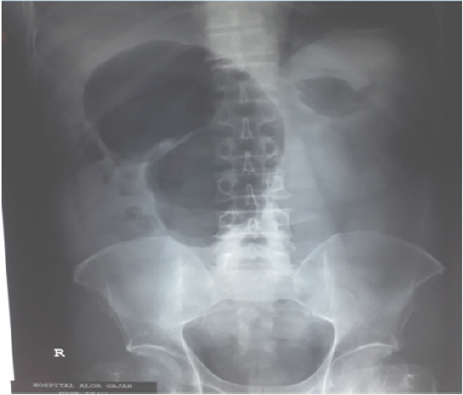

Urgent plain X-ray abdomen showed an inverted coffee bean sign / embryo sign of caecal volvulus and the apex is pointing towards the left upper quadrant of abdomen, caecal dilatation, single air-fluid level, small bowel dilatation and absence of gas in distal colon (Figure 1). His random plasma glucose was 19mmol/L, SpO2 99% under room air. Full blood count: hemoglobin 12.1 g/dl, total white count of 199 x 109/L, platelet count of 398 x109/L. Renal profile: Urea 7.2 mmol/L, Creatinine 104 u mol/L, Na- 128 mmol/L, Cl- 97 mmol/L, K+ 3.5 mmol/L, eGFR 63.4 mL/min/1.73m2. Liver function test: total protein 52 g/L, albumin 25 g/L, globulin 27 g/L, total bilirubin 6.4 u mol/L, Alanine Transferase (ALT) 9 U/L, Aspartate amino transferase (AST) 20, Alkaline phosphatase (ALP) 105 U/L. Coagulation profile: prothrombin time: 11.5sec, INR 1.03 and APTT Ratio was 0.87. His serumCa2+: 1.82 mmol/L, inorganic Phosphate 0.83 mmol/L. His Creatine Kinase (CK) 313, lactate 1.5 mmol/L and amylase 208 U/L (Figure 1).

The patient presented with symptoms of intestinal obstruction. Plain X-ray abdomen revealed a dilatation of localized segment of intestine looked like a shape of an embryo: caecal embro sign (Figure 1) and looks like one of the pictures of caecal volvulus (no.6) of radiology masterclass [8]. However, CT abdomen (ordinary CT) was neither in favour of caecal volvulus nor in favour of appendicitis in this case. Atypical presentation and plain X-ray features of caecal embryo sign mislead to caecal volvulus and management in such line was proceeded. When the abdominal pain was persisting, and laparotomy was carried out and found out to be tip appendicitis attached to the mesentery of small intestine making a hole through which caecum together with small intestine internally herniated resulting small loop obstruction. Juliana M et al. [9] stated that when cecal volvulus is suspected, the absence of distal colonic decompression on CT topograms makes the diagnosis very unlikely. There is short segment focal dilatation of the ascending colon with a maximum diameter of 9.4cm in this patient.